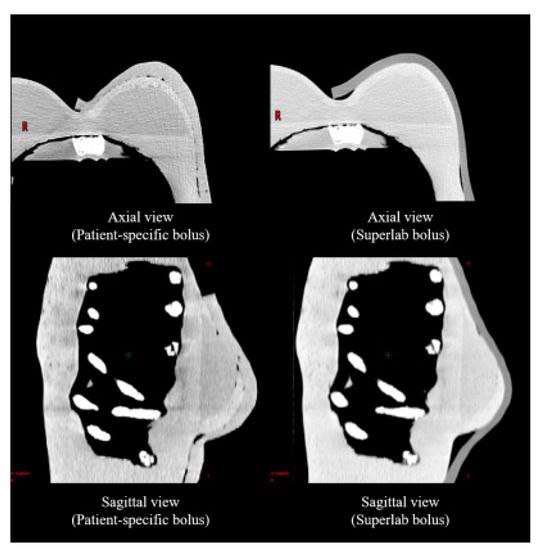

تأتي مادة البولس بأشكال مختلفة، مثل الألواح المرنة أو المواد المطبوعة بتقنية ثلاثية الأبعاد لتتناسب تمامًا مع شكل جسم المريض

.